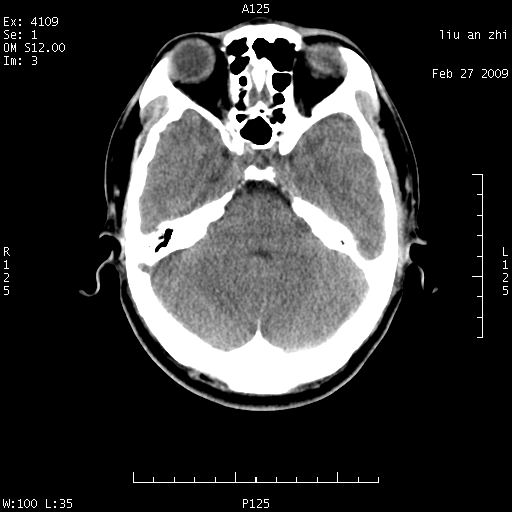

患者:男,32岁 被打伤后3天,自感头昏头痛作头颅ct检查。请大家看一下想什么??

请注意小脑幕!!!

考虑左侧天幕硬膜下血肿。

密度不够,不能诊断sah.正常小脑幕密度可稍高。

左侧天幕硬膜下血肿

考虑小脑幕积血。

ct18448的结果:mri检查左侧天幕下血肿